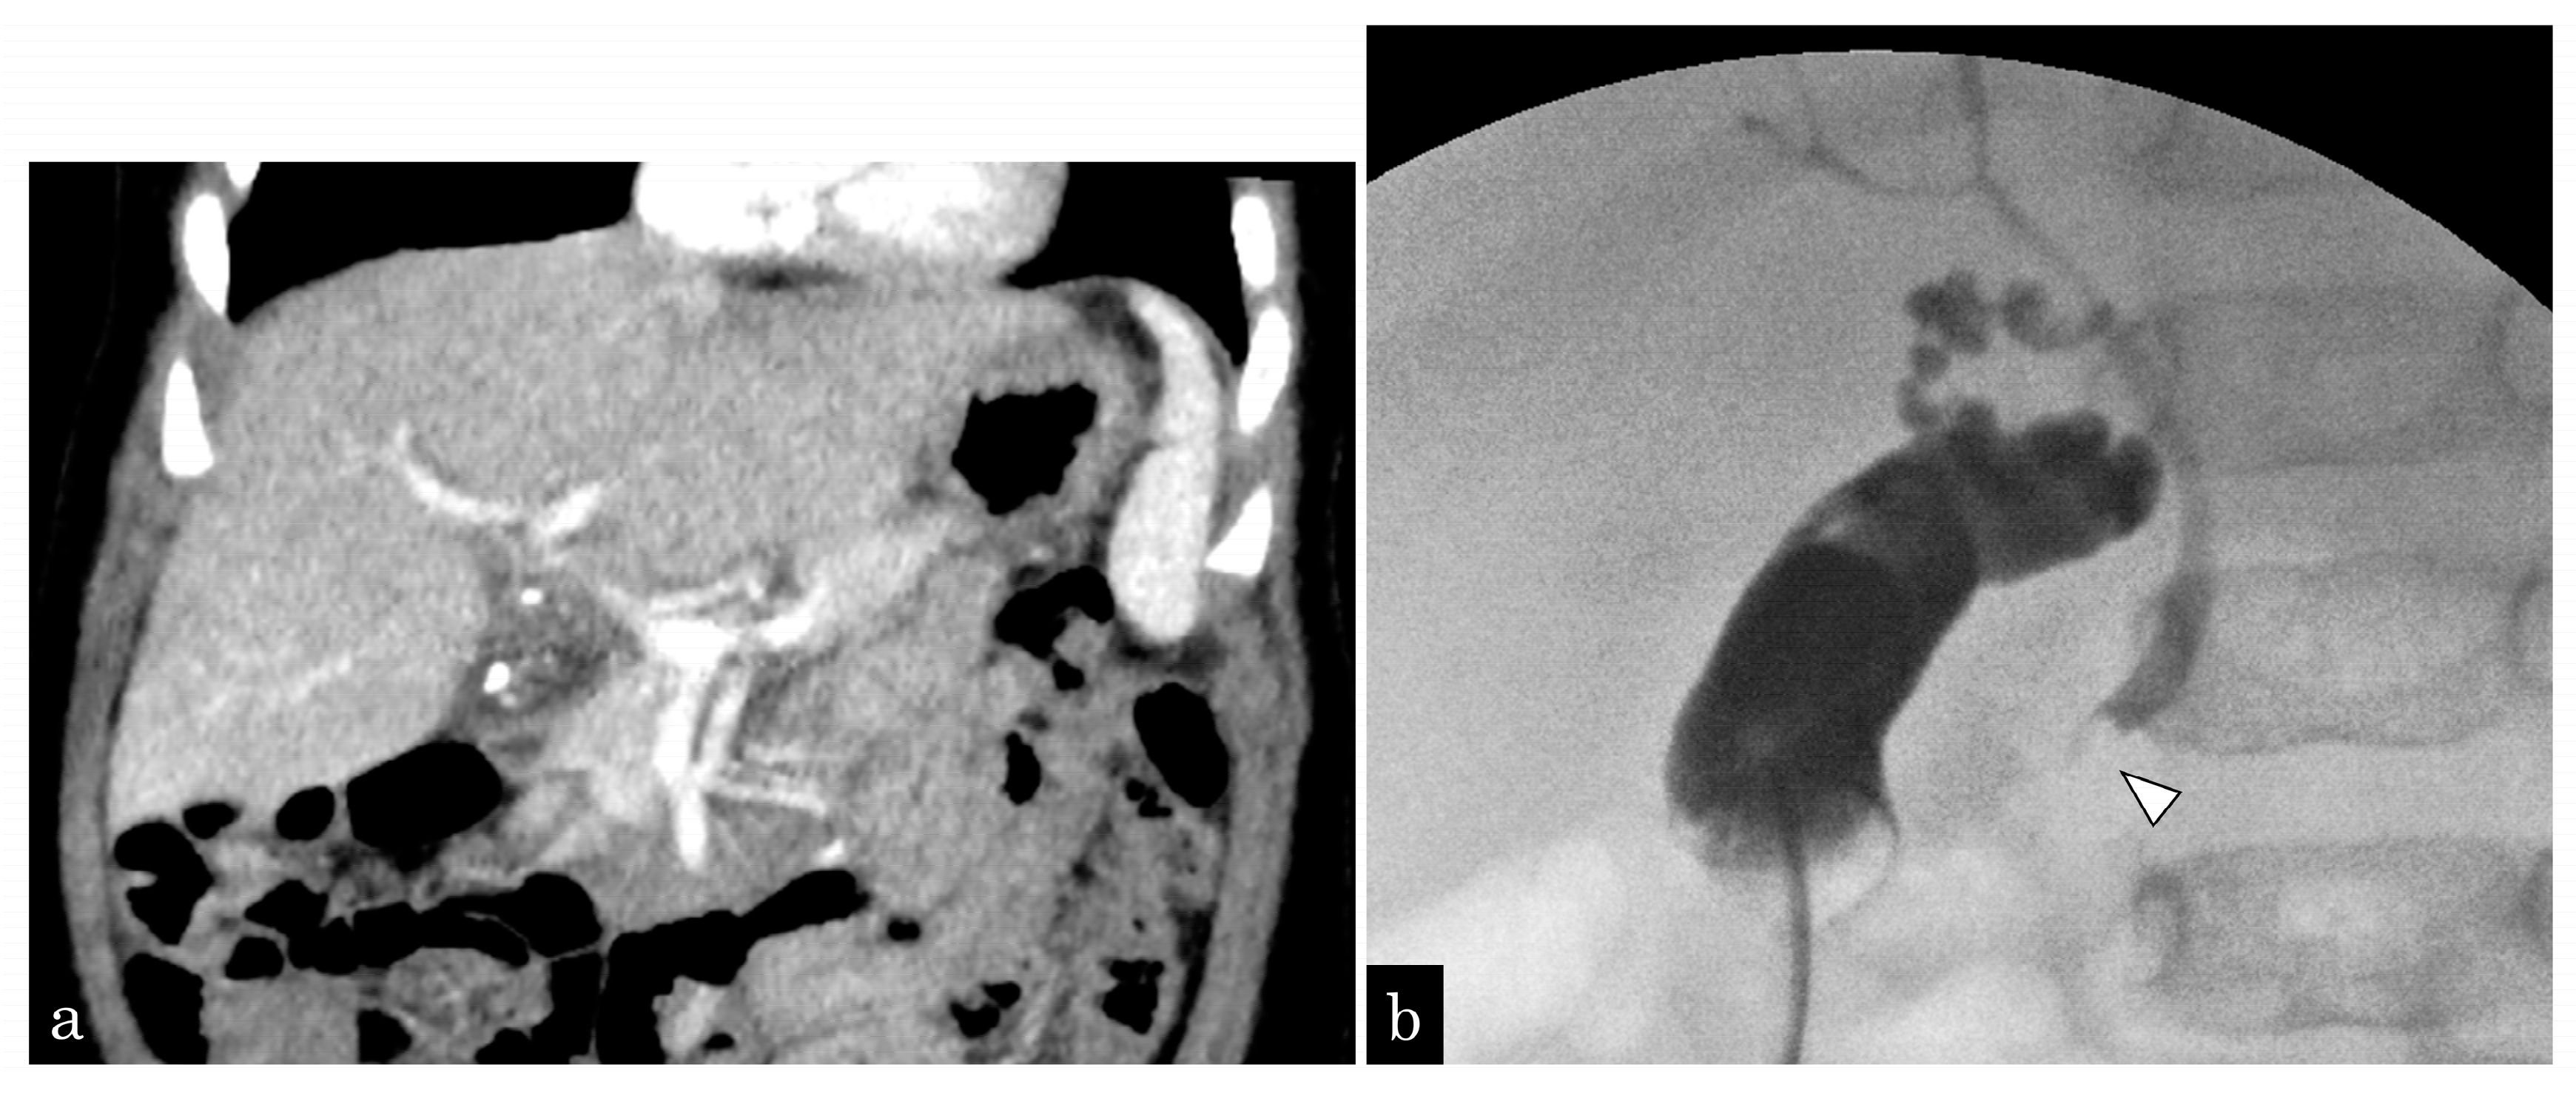

A 5-month-old girl presented with vomiting. Ultrasonography (US) revealed GBSs and gallbladder wall thickness. She presented with sepsis and urgently underwent gallbladder drainage (Figure 1a). During surgery, one CBDS impacting the distal common duct was observed, and an ENBD tube was inserted (Figure 1b). After recovery from cholecystitis and sepsis, EPBD was performed for CBDSs (Figure 2a,b). As the stone was 3 mm in size, the papilla was dilated by 3 mm in 30 s, and the stone was removed by one balloon pulling. The next day, after EPBD, serum lipase (normal range: 13–49 IU/L) levels increased to 1695 IU/L and returned to normal on the fifth day. After pancreatis improved, she underwent a cholecystectomy. The post-EPBD period was 4 months, and her clinical course was uneventful.

Figure 1.

A 5-month-old girl presented with vomiting and revealed gallbladder and common bile duct stones on ultrasonography. (a) Enhanced computed tomography (CT) showing multiple small gallstones and gallbladder swelling. (b) The patient developed septic shock due to cholangitis. Emergency gallbladder drainage was performed, and a bile stone impacting the distal common bile duct (white arrowhead) was noted. A 4-Fr ENBD tube was inserted.